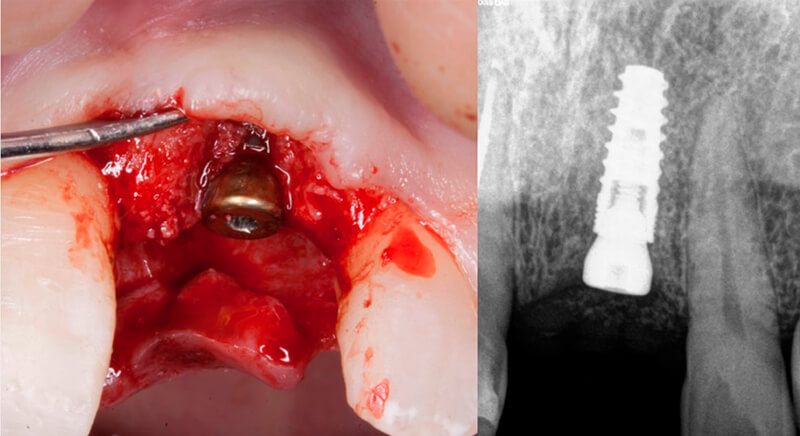

The guided surgery was performed by lifting a full thickness mucoperiosteal flap. A Biomimetic Ocean CC implant, diameter 3.5mm and length 10mm, was inserted using the surgical guide in the ideal three-dimensional position and the defects were regenerated with xenograft and reabsorbable membrane, the nasopalatine duct on the palatine side and the area of dehiscence on the vestibular.

During the same surgical intervention, a short 3mm Avinent healing abutment was positioned and fully covered by the flap. Primary closure was completed and we waited 6 months for the bone graft to mature.